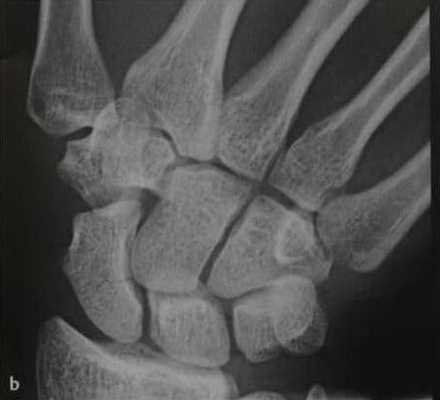

а, b Перелом ладьевидной кости (средняя треть), (а) Дополнительное наложение головчатой кости.

(b) Линия перелома лучше визуализируется при локтевом отведении и локтевом наклоне поверхности запястья.